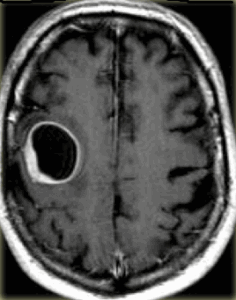

При МРТ головного мозга очаг обычно изоинтенсивен коре мозга. Отёк при МРТ может быть выражен в разной степени. Внутри лейкемического очага, особенно при остром лейкозе, при МРТ головного мозга могут быть кровоизлияния, хорошо видимые на Т1-взвешенных МРТ. При МРТ головного мозга с контрастированием усиление сигнала слабое, неоднородное. Изредка лейкемические очаги вызывают тромбоз венозного синуса, имеющий характерные черты при МРТ головного мозга.

МРТ головного мозга. Очаги лимфолейкоза. Аксиальная Т2-зависимая МРТ.

При МРТ в СПб основную задачу у пациентов с подозрением на гранулоцитарную саркому мы видим в дифференциальной диагностики с другими очаговыми поражениями, особенно лимфомами. МРТ головного мозга при заболеваниях кроветворной системы еще необходимо для исключения инфекционных осложнений. Надо отметить, что в дифференциальной диагностике помогает выявление гранулоцитарных сарком в других местах - коже, орбите, пазухах носа, печени, в мягких тканях шеи, в средостении и легких.